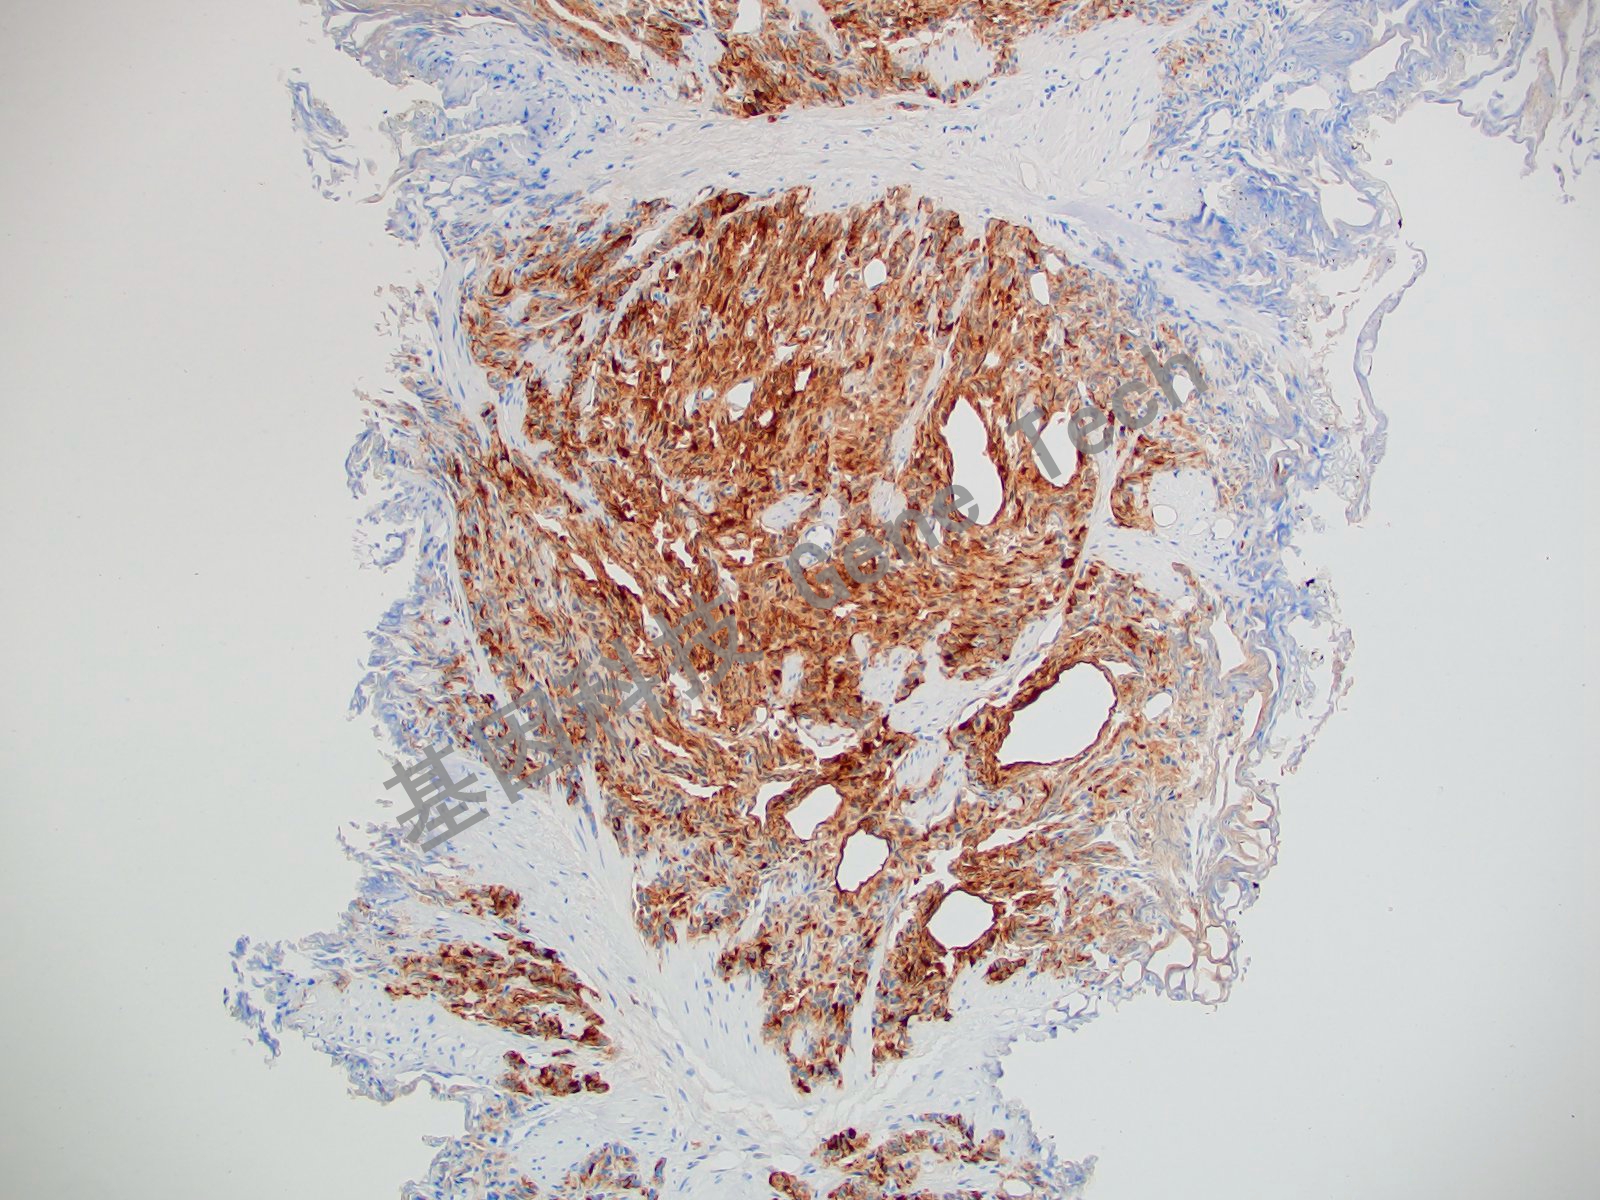

Survivin 兔抗人 存活素(Survivin)抗體試劑(免疫組織化學(xué)法)

| 預(yù)處理:高pH熱修復(fù) | 陽性部位:細(xì)胞漿/細(xì)胞核 | 陽性對照:扁桃體 |

| 前列腺癌石蠟切片,用 Survivin(GT2048)染色,細(xì)胞漿/細(xì)胞核陽性,DAB 顯色。 | ||